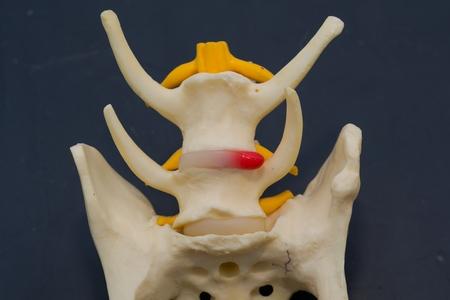

La hernie discale chez le chien

Votre chien a des problèmes à se déplacer ? La hernie discale chez le chien en est souvent responsable. Non traitée, cette pathologie neurologique cause perte de mobilité, voire paralysie. D’où l’utilité de la soigner au plus vite ! Comment reconnaître cette affection canine ? Quelles en sont les causes ? Quels traitements proposer ? Mouss répond à vos questions.